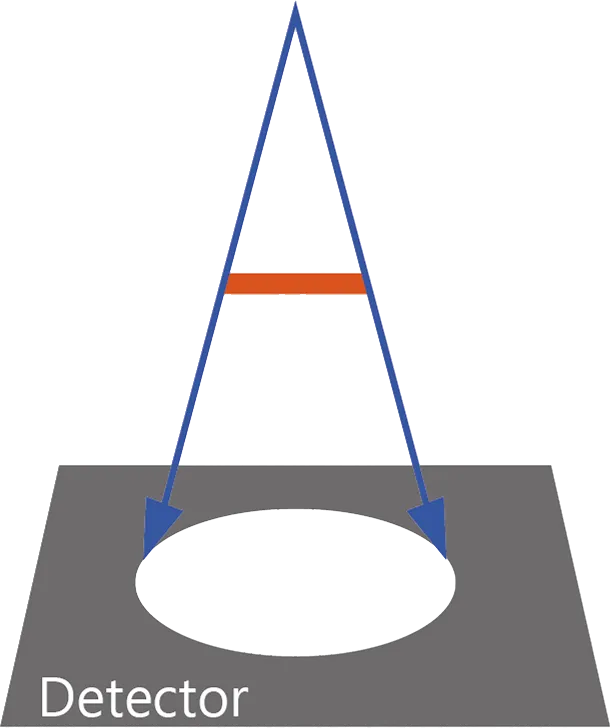

- - Размытые границы - детектор

- - Эффект размера фокального пятна

- - Спроектирован для создания точных изображений